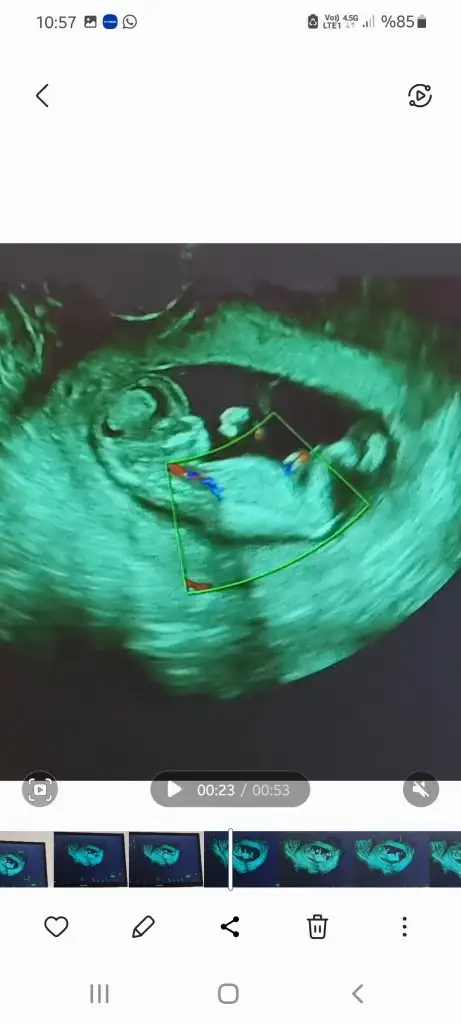

Yaaa biliyordum :) Hayırlı olsun diloşcum. Çok çok sevindim.Günaydıınn herkese, ben ikili testten geldim şuanlik bi sorun görünmüyor kan verdim 1 haftaya çıkar dediler. Ense 1.04 çıktı

Bu da benim kızçeGünaydıınn herkese, ben ikili testten geldim şuanlik bi sorun görünmüyor kan verdim 1 haftaya çıkar dediler. Ense 1.04 çıktı

Bu arada daha erken, kıza benziyor dedi doktor. Bi kızçe haberi de benden gelsin o zaman

Bu da benim kızçe